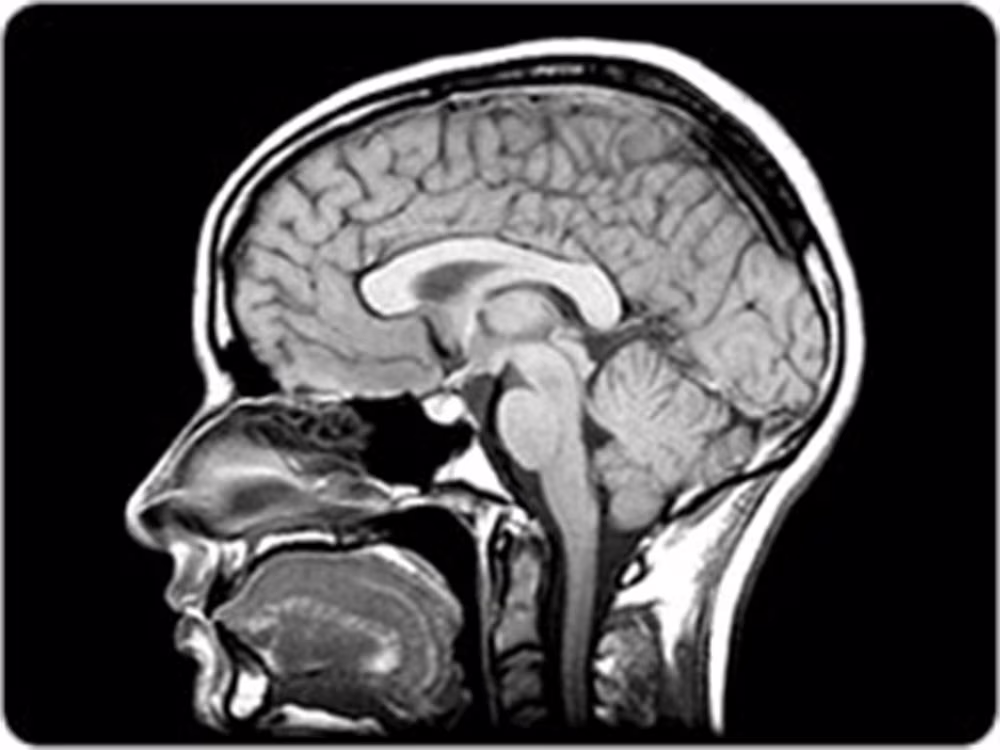

La risonanza magnetica, il cui funzionamento è stato trattato in maniera più approfondita in un nostro precedente articolo, è una tecnica di imaging non invasiva che trova numerose applicazioni diagnostiche, soprattutto nello studio dell’encefalo.